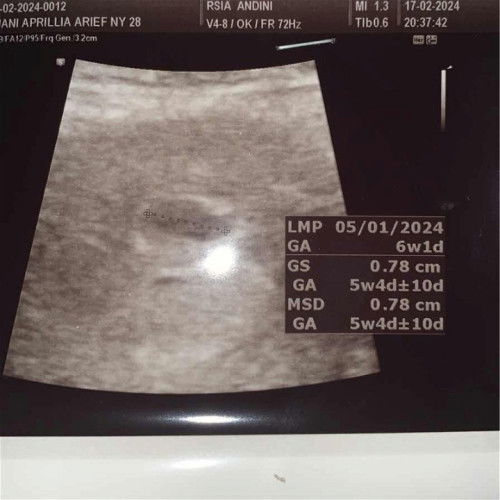

Hamil 6 weeks

Bun, ada yang sama gak 6 minggu tapi masih kantung aja, kecil banget dan gak ada janin? 😔😔 kantungnya masih 0,78 cm. dokternya langsung kaya mau nyerah gtu, tapi akhirnya dia nyuruh 10 hari balik lagi buat dicek. Kalau gk ada perkembangan, nanti digugurin. Sedih banget 😔😔